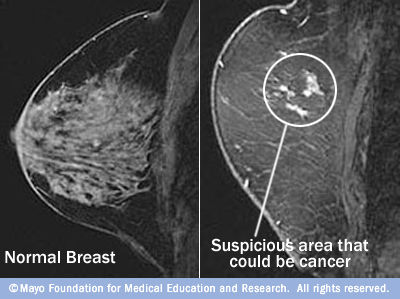

1. MRI

1. How it works

1. The MRI scanner captures the energy and creates a picture of the scanned tissues

1. Hydrogen atoms naturally exist in the body. Radio waves redirect the alignment of the hydrogen atoms in the body and and analyze the energy different tissues emit when the hydrogen atoms return to their typical alignment in the body

2. What it shows

1. Organs, soft tissues, bone

2. Uses

1. Evaluate organs of the body/abdomen, pelvic organs (bladder, reproductive organs), blood vessels, and lymph nodes

1. Diagnose and monitor treatments

2. MRI diagnosing breast cancer